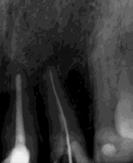

Estudios radiográficos de inicio

En la radiografía lateral de cráneo tenemos (Figura 7) la clase III esquelética con un ANB de -1, hiperdivergencia, aumento de la altura facial inferior, proclinación de los incisivos superiores con 1 a plano palatino de 133°, línea roja sobre la longitud del incisivo superior.

En la radiografía panorámica (Figura 8) se observan 32 dientes presentes

en boca, con la rehabilitación de los órganos dentarios por oclusal, con obturaciones de amalgamas, e incrustaciones, y divergencias radiculares inadecuadas.

Figura 7. Radiografía lateral de cráneo. Figura 8. Radiografía panorámica.